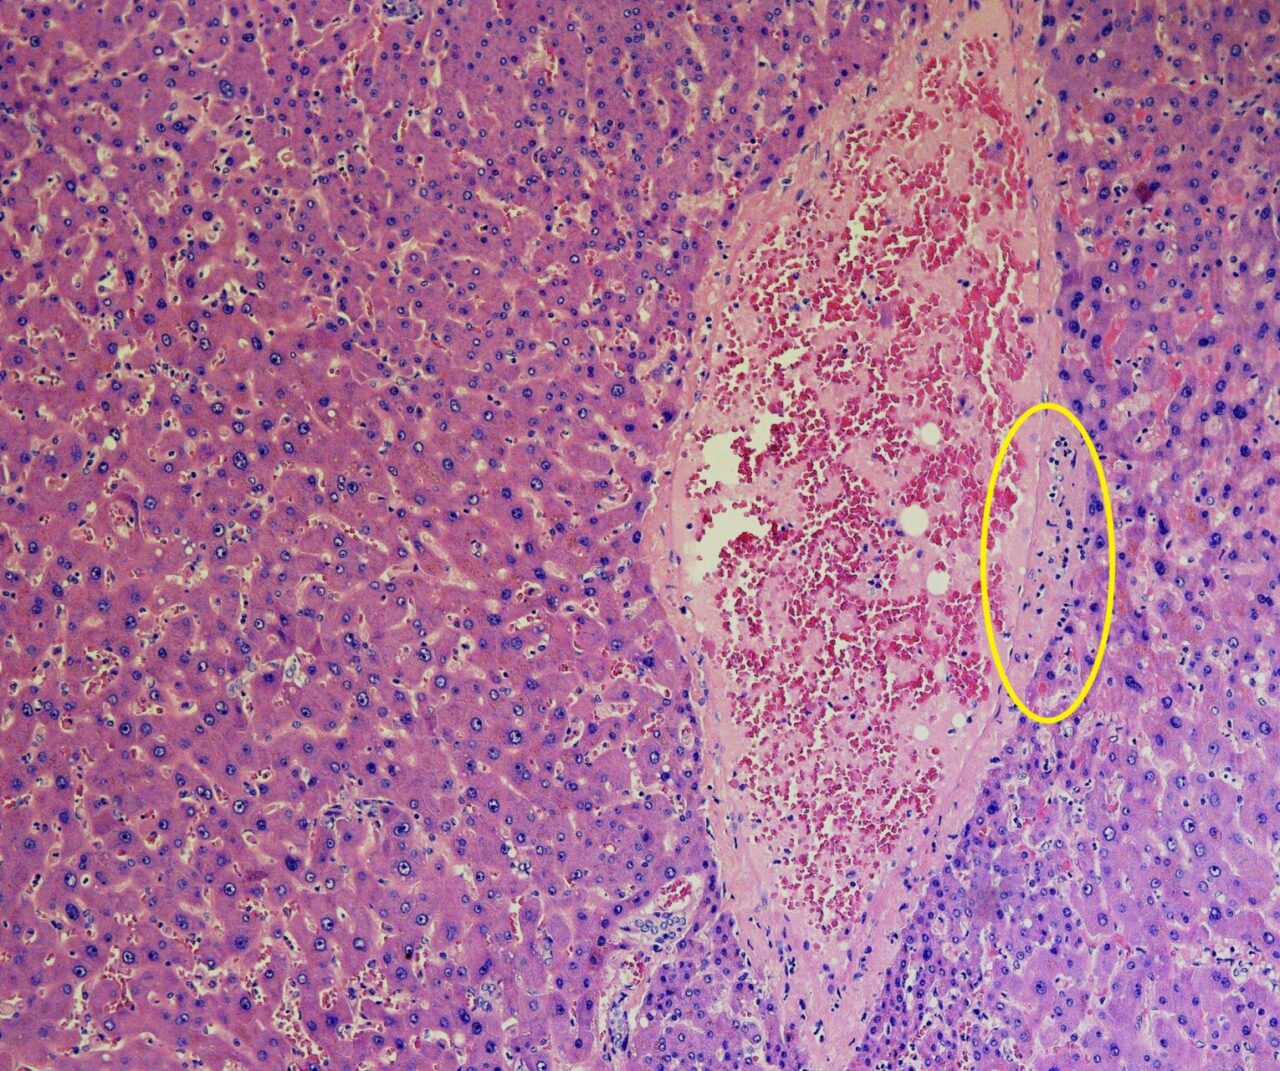

La collaborazione tra i ricercatori della prestigiosa Università di Yale, New Haven, Connecticut (Usa) e l’Ospedale Papa Giovanni XXIII ha permesso, per la prima volta, di analizzare e soprattutto riprodurre il meccanismo patologico con cui il virus causa un danno del fegato nei malati di Covid-19. Questo studio conferma il ruolo-chiave della citochina IL-6 e della endoteliopatia, cioè l’infiammazione delle pareti dell’endotelio che riveste i vasi sanguigni, responsabile del danno epatico associato a forme gravi e mortali di Covid-19.

Il virus Sars-Cov-2 induce cioè le cellule dell’endotelio dei vasi sanguigni che irrorano il fegato a produrre una proteina chiamata interleuchina IL-6, che in situazioni normali agisce con funzione di regolazione dei processi immunitari. Quando la sua produzione è sregolata ed eccessiva può portare a stati infiammatori anomali. Nel caso del Covid-19, questa tempesta porta allo stato infiammatorio (endoteliopatia) e alla coagulazione del sangue all’interno dei vasi.

Per lo studio sono stati analizzati i campioni del fegato di 43 pazienti morti di Covid a Bergamo nella primavera del 2020, ma anche le radiografie effettuate dall’unità dell’ospedale in quello stesso periodo. Lo studio è fondamentale in quanto dimostra come le coagulazioni anomale, che portano poi ai casi di trombosi che generano la forma grave della malattia, potrebbero essere fortemente legate all’azione che il virus ha su quest’organo specifico del nostro corpo, motivo per cui si metterebbe l’accento sul ruolo dell’endoteliopatia come principale causa di danno epatico rispetto alla coagulopatia, proprio perché sarebbe la causa di quest’ultima.